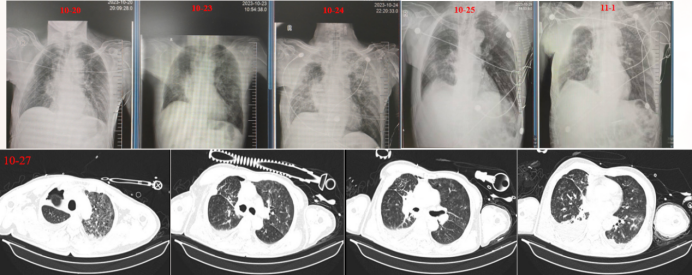

117复查CT双肺炎症明显吸收,腹部未见病理性表现(图4)。多次复查心脏彩超未见瓣膜赘生物。后患者热峰略下降。使用复方磺胺甲后,患者出现白细胞下降趋势, 1111PCT可回落至0.93 ng/ml1112体温再次升高至≥38.5℃, 分别于11121115复查外周血及中心静脉导管血培养均提示嗜麦芽窄食单胞菌(分别记录为图5中的“嗜麦芽5、嗜麦芽6、嗜麦芽7), 患者的肺炎及呼吸衰竭逐步控制, 胃肠功能稳定, 可耐受肠内营养。1115拔除气管插管, 拔管后患者出现声音嘶哑, 纤支镜可见右侧声带活动欠佳, 与胸外科手术医生沟通, 考虑为手术相关右侧喉返神经损伤。

图片

4  117胸部+腹部CT